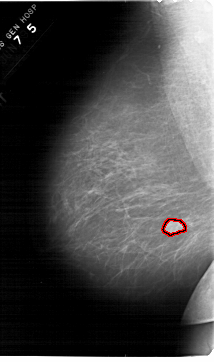

A_1567_1.LEFT_MLO

LEFT_MLO LINES 6871 PIXELS_PER_LINE 4051 BITS_PER_PIXEL 12 RESOLUTION 43.5 OVERLAY

FILE: A_1567_1.LEFT_MLO.OVERLAY

TOTAL_ABNORMALITIES 1

ABNORMALITY 1

LESION_TYPE MASS SHAPE LOBULATED MARGINS OBSCURED

ASSESSMENT 4

SUBTLETY 4

PATHOLOGY BENIGN

TOTAL_OUTLINES 1

BOUNDARY